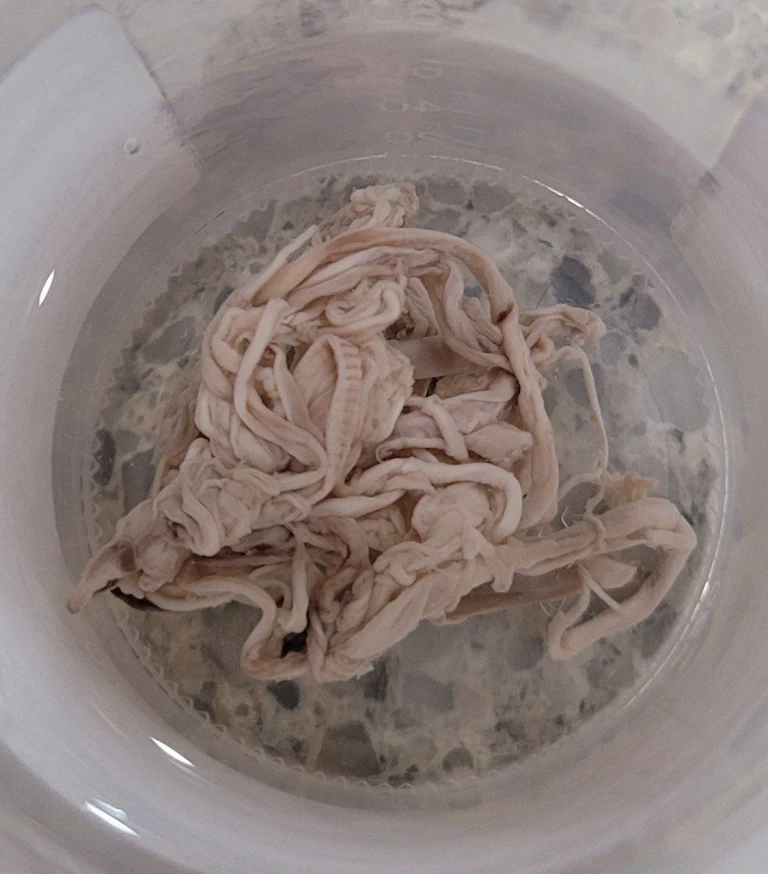

Blood clots found by morticians have been sent all over the world to be studied by independent teams.

The only thing that is for sure is that something is taking the injected metals and building them into “killer clots” throughout the body.

These clots have substances and structures inside of them that are “unidentifiable” and cannot be explained by anyone. But they are obviously designed to kill the host body that receives the injections.